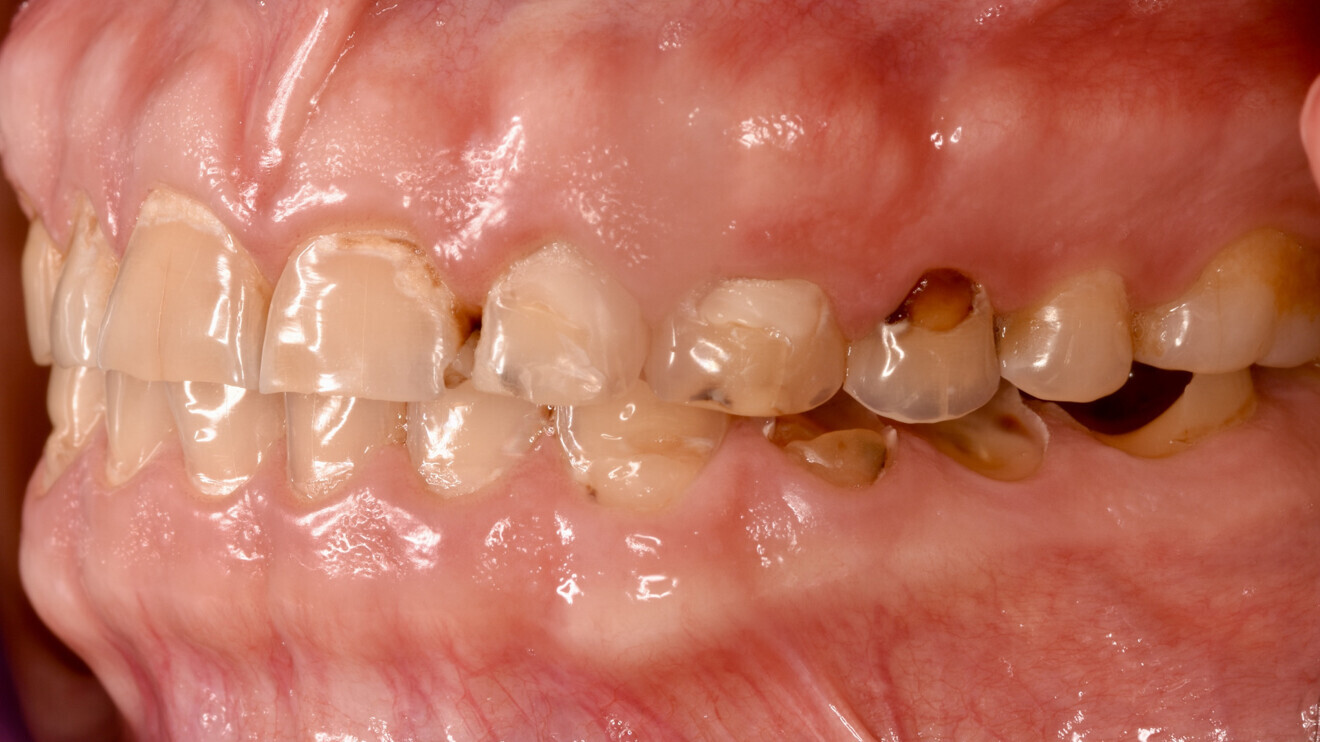

Fig. 1b: Initial situation. Left lateral view.